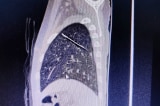

Kim may rỉ sét nằm sâu trong nhu mô phổi bé trai 4 tuổi

Ngã gãy xương đòn trái, qua chụp XQ kiểm tra lồng ngực, bé trai 4 tuổi được phát hiện dị vật hình dạng kim may nằm sâu trong phổi trái.